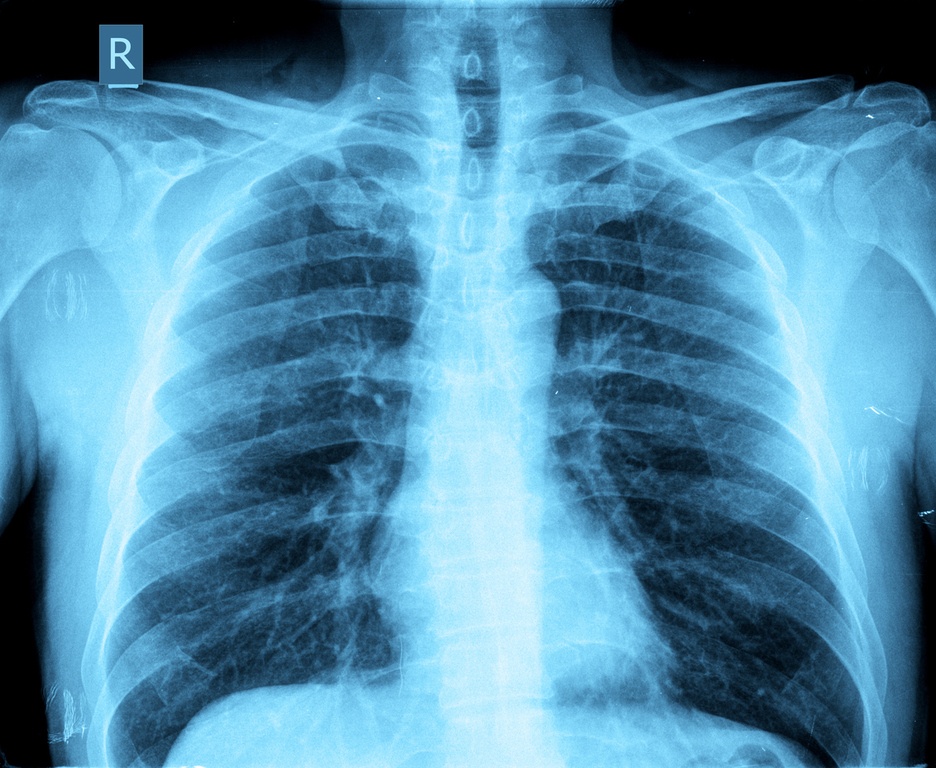

Detectar de manera temprana el cáncer de pulmón puede salvar nuestras vidas, el problema es que los primeros síntomas son casi indetectables, o las personas suelen asociarlos con otra enfermedad. Ante cualquier indicio debemos acudir con el doctor.

A continuación te diremos cuáles son los síntomas más comunes de las primeras etapas del cáncer de pulmón:

Tos persistente

La revista Médica Surgery señaló que en el 75% de los casos, este es un síntoma muy alarmante y se produce por la irritación de conductos.

Respirar con dificultad

La respiración suele cambiar por la obstrucción de los tumores. Ciertas actividades se vuelven muy difíciles de realizar, como subir escaleras.

Dolor de pecho

Muchas personas experimentan un dolor intenso en el pecho sobre todo cuando tosen o respiran profundamente e incluso cuando ríen.

Tos con sangre

La gente puede tener tos con sangre y no necesariamente significa indicios de cáncer, lo más recomendable es siempre asistir con un especialista.

Neumonía o bronquitis

Cuando se padece cáncer de pulmón las enfermedades se hacen más comunes y agudas.